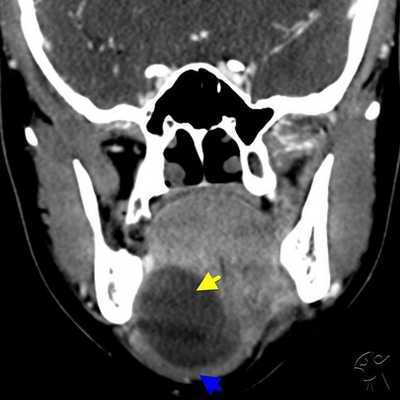

КТ-признаки слюннокаменной болезни

Отечность, увеличение околоушной и поднижнечелюстной областей, не проходящие после приема фармацевтических препаратов - показание к лучевой диагностике. Симптомы обуславливает не только сиалоаденит. Слюннокаменная закупорка (сиалолитиаз) определяется после КТ-сиалографии по следующим признакам:

Тонкосрезовая СКТ головы и слюнных желез с трехмерным моделированием (3D) создает пространственную структуру, с помощью которой врачи устанавливают внутрипротоковое расположение камня.

Применение обследования помогает обнаружить аденокарциному слюнной железы - злокачественную опухоль, склонную к быстрому прогрессированию, прорастанию близлежащих тканей. Онкология чаще обнаруживается случайно, так как не имеет специфических внешних признаков.

КТ-проявления болезни Шегрена

Аутоиммунное поражение железистой ткани сопровождается симметричным изменением органов (с обеих сторон). Использование КТ-сиалографии позволяет выявить специфические проявления нозологии:

- Зернистость поднижнечелюстной и околоушной железистой ткани;

- Снижение плотности;

- Шейная лимфаденопатия;

- Псевдолимфомы;

- Уменьшение размеров слюнных желез.

К аутоиммунному поражению может присоединяться бактериальная или грибковая инфекция околоушно-жевательной области. Томограммы показывают аналогичные нарушения жевательной мышцы, крыловидного пространства, поднижнечелюстной полости.